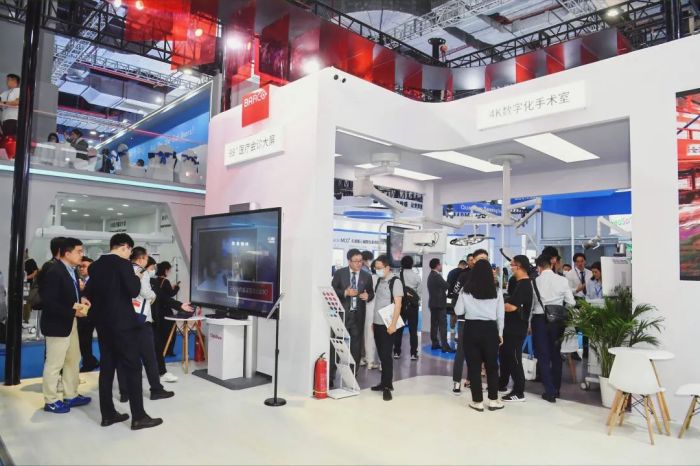

2023年5月14日,第87届中国国际医疗器械博览会(CMEF)在上海隆重开幕。巴可公司以“精准医疗 影像先行”为主题,携旗下众多医疗专业解决方案亮相。其中,4K数字化手术室和一体化阅片影像中心两个解决方案备受瞩目。展出期间,众多行业专家和观众莅临巴可展台进行体验和咨询,这些解决方案将帮助医疗行业更好地实现精准医疗及数字化改革,为医疗设备行业注入新的活力和能量。